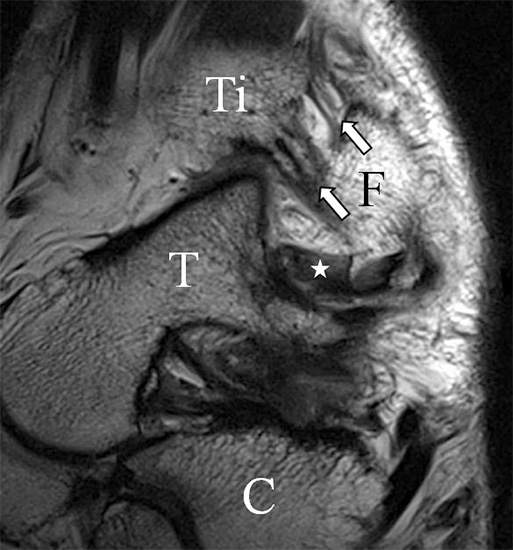

Das Ligamentum fibulotalare anterius entspricht einer bifaszikulären Struktur (Abb. 2 a) mit interponierendem fibrovaskulärem Gewebe (S. K. Sarrafian (ed). 2003). Es gibt jedoch Variationen der Ligamentanatomie. In 55% liegt das LFTA als bifaszikuläres Band (Abb. 2 a), in 9% als monofaszikuläre Bandstruktur (Abb. 2 b) und in 36% als multifaszikuläre, striäre Variante (Abb. 2 c) vor 3.

PD fs HR axial. Klare Darstellung eines filigranen, knapp über 1 mm breiten LFTA (Pfeil). Fibula (F).

Abbildung 3

Das LFTA verbindet die antero-inferiore Fibulaspitze mit dem Processus lateralis tali und inseriert hier an einem oder zwei kleinen Tuberkeln 3. Der in Neutralposition horizontale Verlauf erleichtert die kernspintomographische Darstellung in dieser Standardebene. Das LFTA weist durchschnittlich eine Breite von knapp über 2 mm auf 4. Somit sind bei einer Routinedarstellung in 3 mm Schichtdicke Anschnittsphänomene, die die Diagnostik erschweren, regelmäßig anzutreffen. Dementsprechend sind auch die ligamentären Subfaszikel nicht zu differenzieren. In koronarer Darstellung ist dies aufgrund der hohen Auflösung in der Schichtebene jedoch möglich (Abb. 2 a-c), wobei hier wiederum eine Integritätsbeurteilung des Bandes erschwert ist. Unter Verwendung hochauflösender Techniken im Millimeterbereich (Schichtdicke) sind hingegen auch in der axialen Ebene die subfaszikulären Strukturen zu beurteilen (Abb. 3).